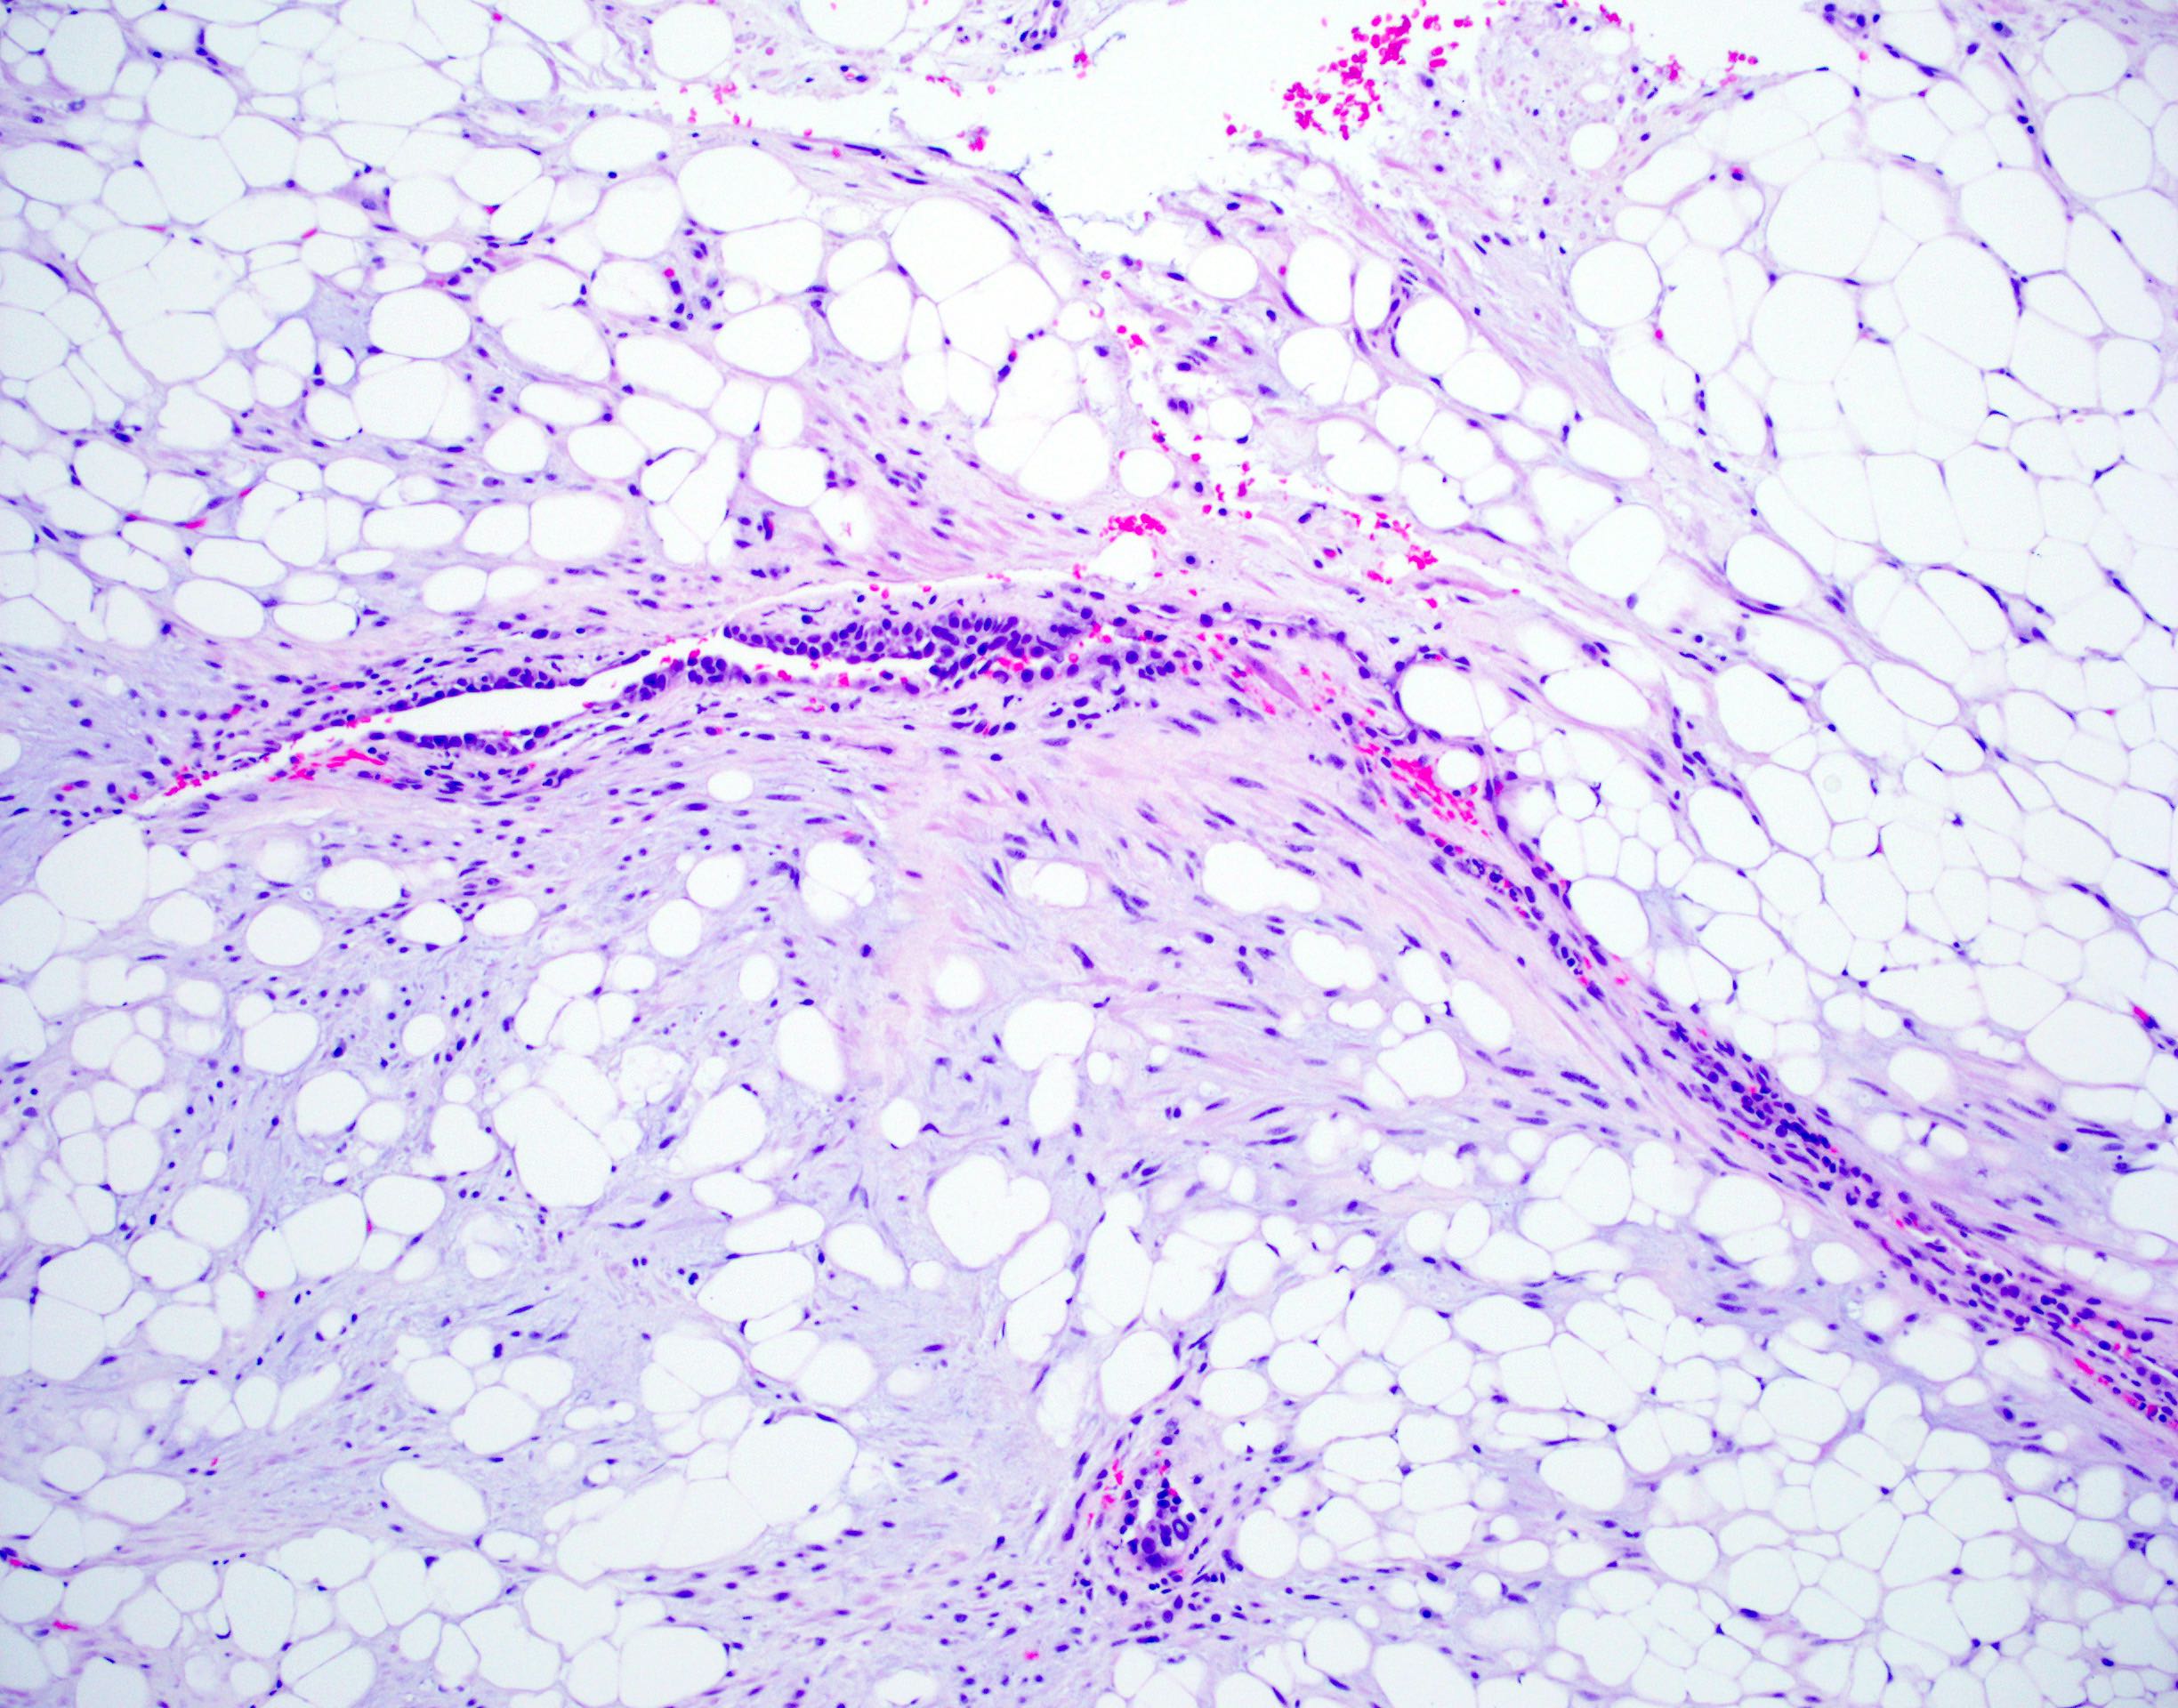

Microscopic (histologic) description

- Composed predominantly of varying degrees of mesenchymal tissue: hyaline cartilage, fat, smooth muscle and bone

- Other connective tissue elements may be present, represented by bland spindle cells, fibrous tissue or myxoid change

- Variably conspicuous, entrapped benign epithelial cells

- Reference: Thorax 1987;42:790

Microscopic (histologic) images

Contributed by Hui-Hua Li, M.D., Ph.D. and Jefree J. Schulte, M.D.

Contributed by @Andrew_Fltv on Twitter